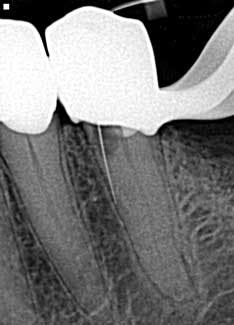

• Missed canals

Know your tooth anatomy and the possible variations of the canals (figure 2). The molars present with the most diverse canal composition—“additional canals in the mesial roots of maxillary molars and the distal roots of mandibular molars are the most frequently missed” (2)—but even the premolars and incisors can prove to be a formidable foe. Remember the article by David Landwehr, DDS, MS, titled “The myth of ‘easy’ root canals in endodontics”? Read it if you haven’t. Lastly, don’t skimp on your occlusal access and use magnification.